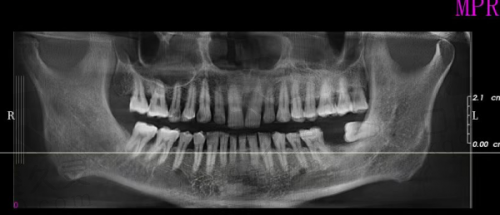

我第一次走进南昌虹桥口腔医院,就被医院整洁明亮的环境所吸引。前台的工作人员非常热情,在了解我的需求后,快速为我安排了挂号和就诊。等待就诊的过程中,医院还提供了舒适的休息区域和免费的茶水,让我感到非常贴心。特别快,我就见到了为我接诊的医生。医生非常和蔼可亲,他详细地询问了我的病史和牙齿情况,然后为我进行了全方面的口腔检查。检查过程中,医生一边操作一边向我解释每一个步骤,让我对自己的牙齿状况有了更清晰的了解。

检查结束后,医生根据我的口腔情况和个人需求,为我制定了个性化的种植牙方案。他向我介绍了不同品牌和型号的种植体,并详细说明了它们的优缺点和适用情况。在选择种植体的过程中,医生没有强行推销,而是耐心地听取我的意见,根据我的经济状况和牙齿条件,为我推荐了更适合我的种植体。整个方案制定过程非常透明,让我对种植牙的费用、流程和预期成效都有了明确的了解。